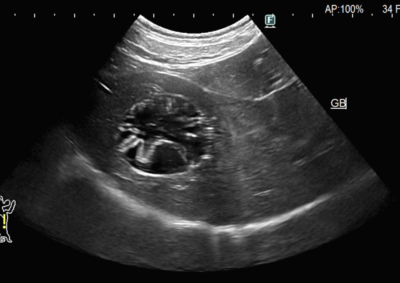

軟部組織外科 注意 ボタンをクリックした先に、治療中および手術中の画像が説明で使用されている場合がございます。 そのような画像に弱い方は閲覧なさらないようお願いいたします。 軟部組織外科 犬の唾液腺切除 軟部組織外科救急・集中治療 猫の腸重積 軟部組織外科呼吸器外科 複数の肺葉捻転 軟部組織外科 肝臓・脾臓過形成病変 軟部組織外科 胆嚢粘液嚢腫 軟部組織外科 尿道狭窄に対する経骨盤尿道瘻設置術 軟部組織外科救急・集中治療 猫の両側尿管閉塞 軟部組織外科救急・集中治療 猫の腸閉塞(毛玉) 軟部組織外科 唾液腺嚢胞 軟部組織外科腫瘍外科 断脚手術(軟部組織肉腫) 軟部組織外科腫瘍外科 猫の肝葉切除術(内側左葉) 軟部組織外科救急・集中治療 腸閉塞・腸切開 <12345678> 症例カテゴリー 放射線治療整形外科軟部組織外科脳神経外科内科腫瘍外科救急・集中治療リハビリテーション科腫瘍内科内視鏡科脳神経科呼吸器外科中医・漢方猫の腎移植循環器科